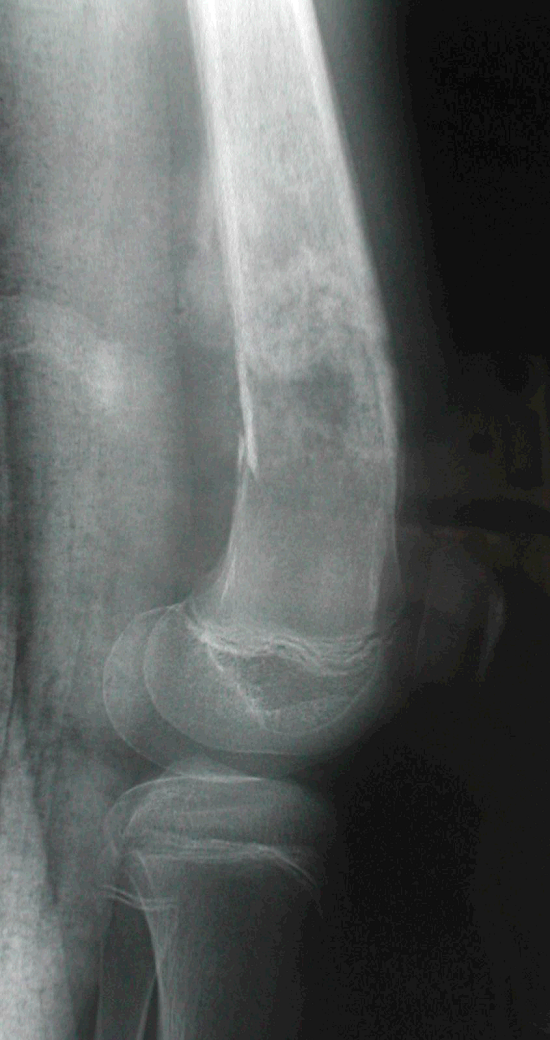

2、病例2:女 10岁 左股骨下端普通型骨肉瘤并病理性骨折,大剂量化疗后行肿瘤边缘切除定制型假体置换术,术后局部复发截肢,2年后肺转移死亡。

图 7术前X线片

a:正位 b:侧位

图 11 术后7个月局部复发